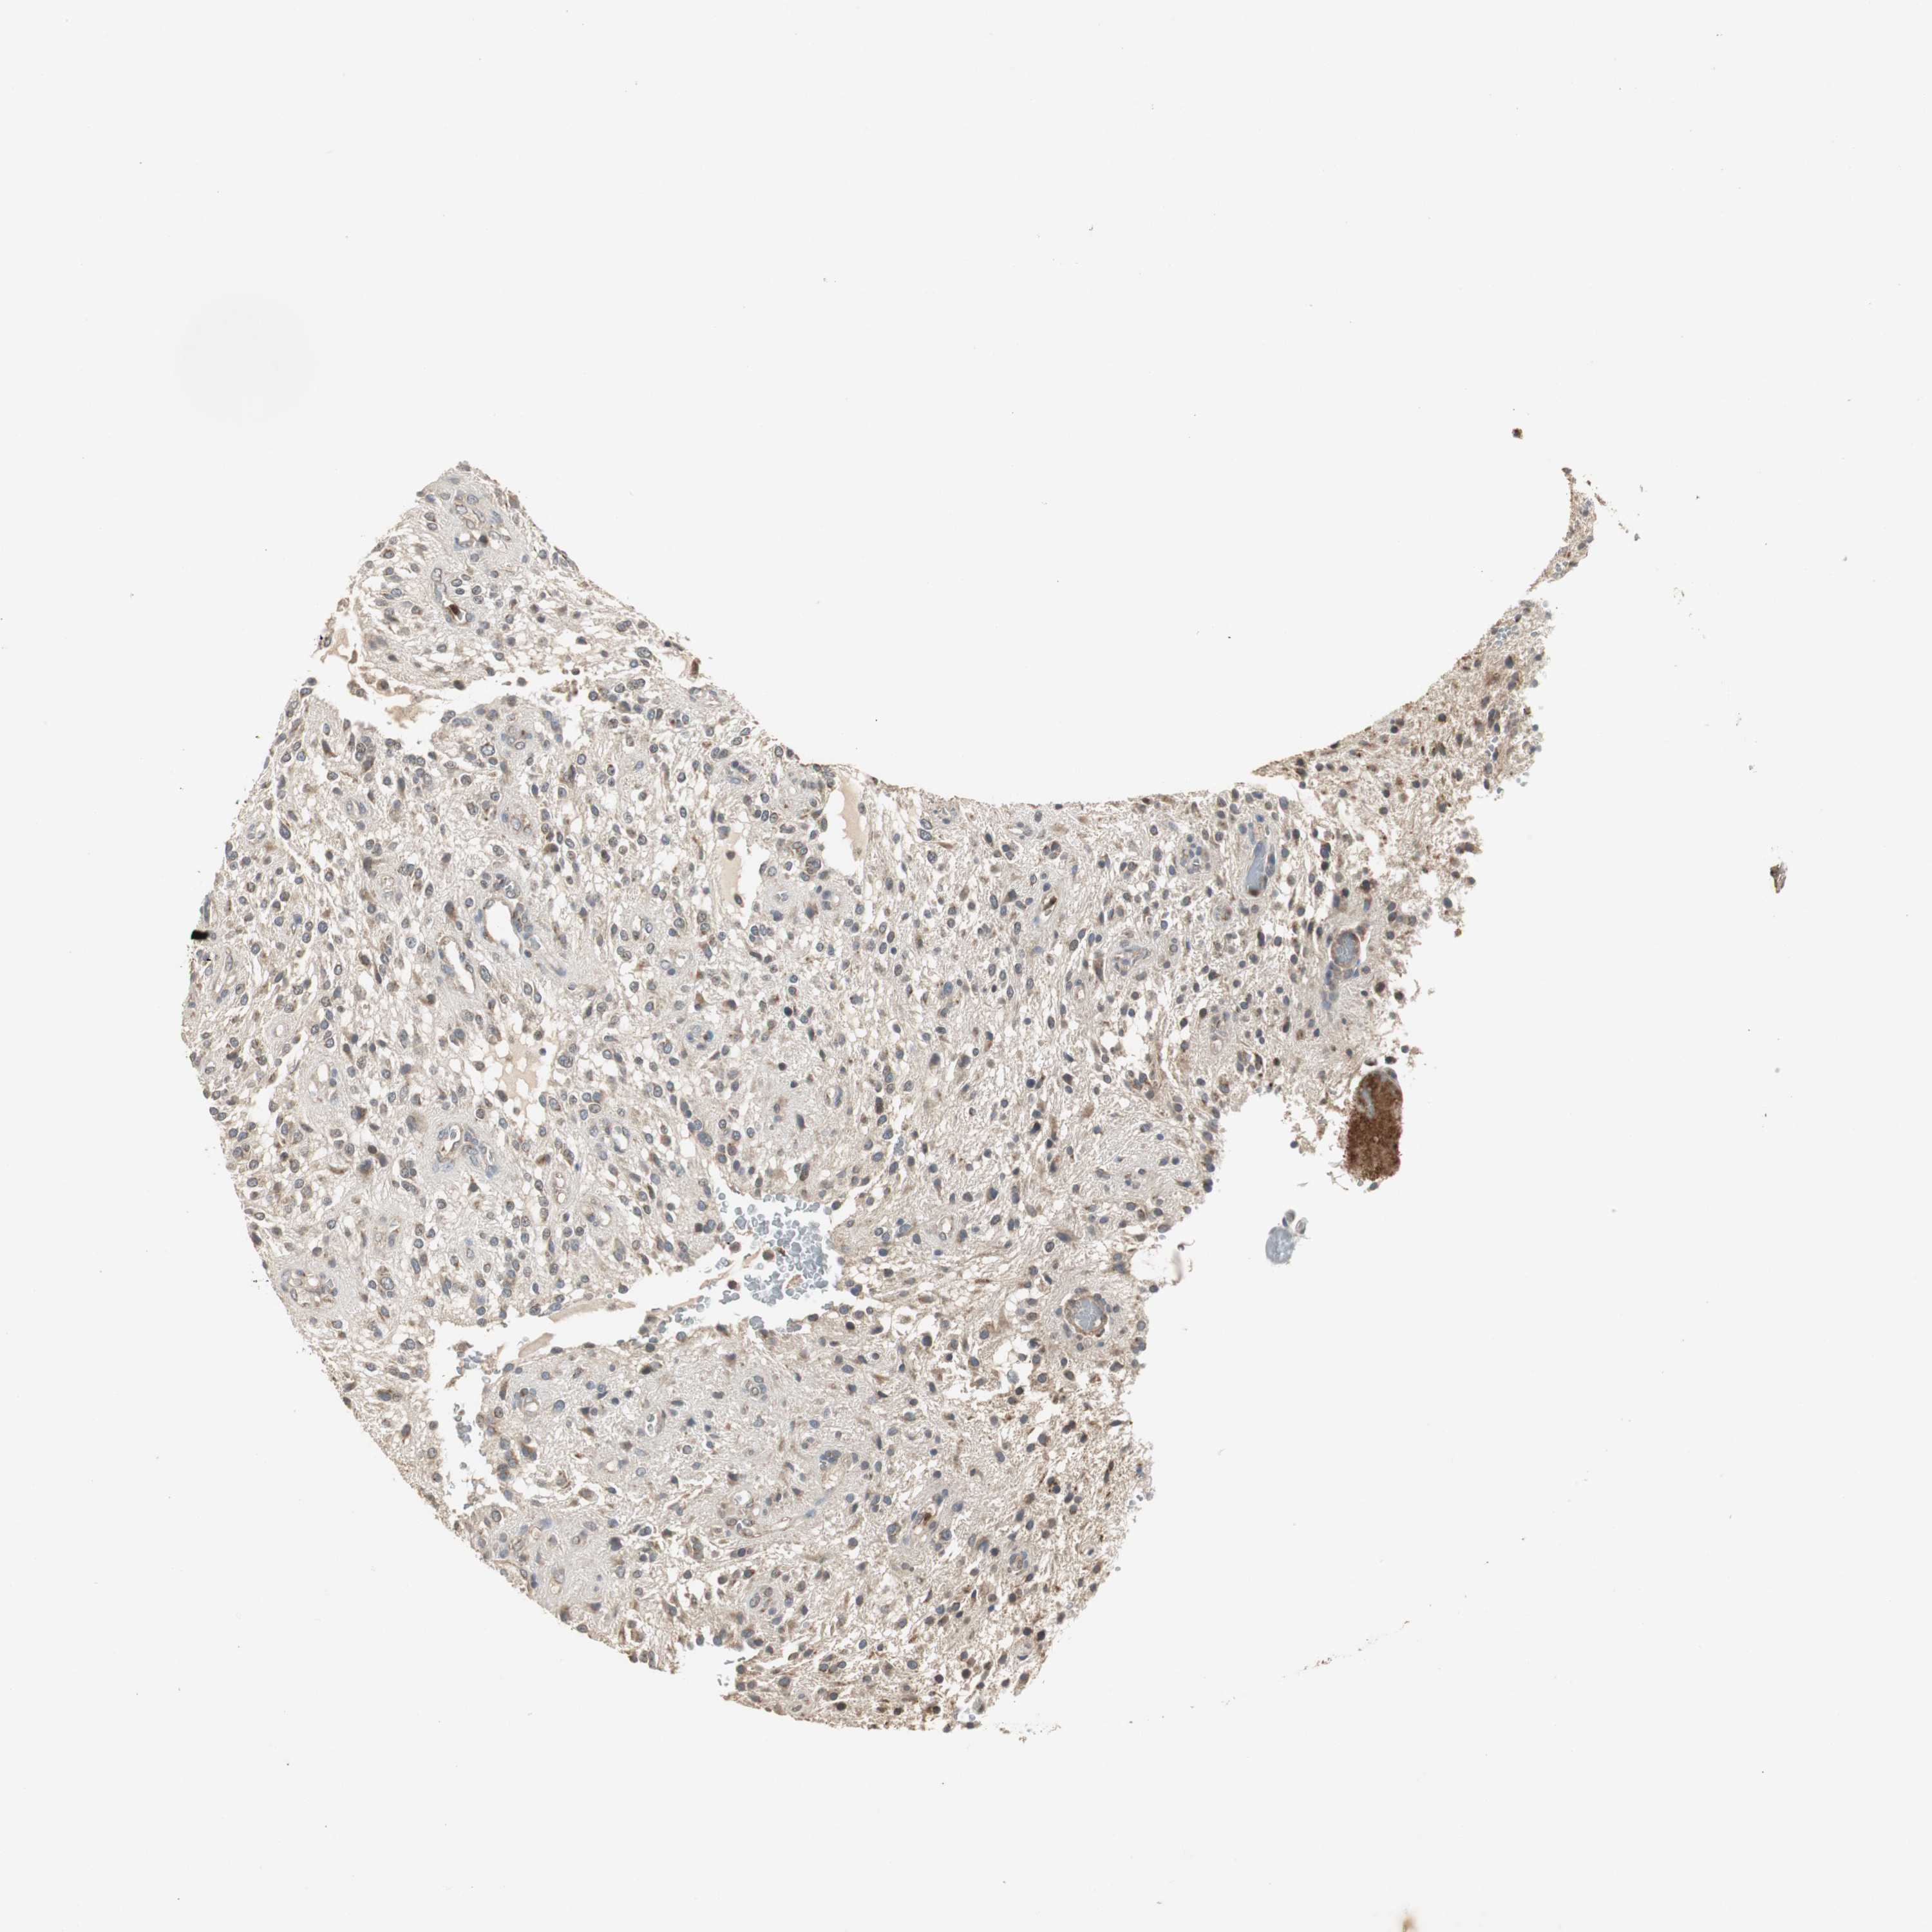

GLIOMA - Protein expressioni

A mouse-over function shows sample information and annotation data. Click on an image to view it in a full screen mode. Samples can be filtered based on level of antibody staining by selecting one or several of the following categories: high, medium, low and not detected. The assay and annotation is described here.

Note that samples used for immunohistochemistry by the Human Protein Atlas do not correspond to samples in the TCGA dataset.

Antibody stainingi

Antibody staining in the annotated cell types in the current human tissue is reported as not detected, low, medium, or high, based on conventional immunohistochemistry profiling in selected tissues. This score is based on the combination of the staining intensity and fraction of stained cells.

Each image is clickable and will lead to virtual microscopy that enables deeper exploration of all samples and also displays staining intensity scores, fraction scores and subcellular localization as well as patient and tissue information for each sample.

Antibody HPA006514

Staining

High

Medium

Low

Not detected

Intensity

Strong

Moderate

Weak

Negative

Quantity

>75%

75%-25%

<25%

None

Location

Nuclear

Cytoplasmic/membranous

Cytoplasmic/membranous,nuclear

Glioma, malignant, High grade

Glioma, malignant, NOS